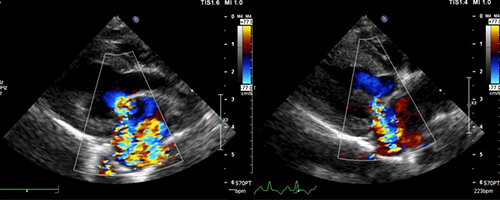

수술 전/후 초음파

수술 전/후 초음파 이미지

이미지 준비 중